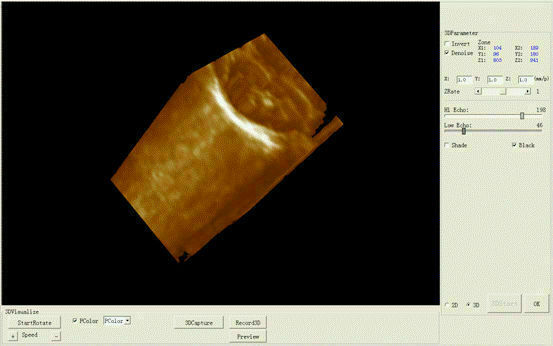

The new Portable Laptop Digital Ultrasound Scanner features a 3.5MHz micro convex probe for versatile imaging capabilities. This compact machine is designed for high-quality diagnostics in various medical settings, providing detailed ultrasound images. Its lightweight design and user-friendly interface make it ideal for healthcare professionals who require mobility and ease of use. The scanner is suitable for a range of applications, ensuring accurate assessments and improved patient care. Overall, it's a reliable solution for modern medical imaging needs.